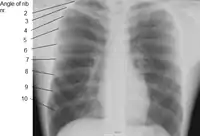

Numbering order of the vertebrae of the human spinal column

There are thirty-three vertebrae in the human vertebral column. The rib cage is associated with TH1−TH12. Ribs are described based on their location and connection with the sternum. All ribs are attached posteriorly to the thoracic vertebrae and are numbered accordingly one to twelve. Ribs that articulate directly with the sternum are called true ribs, whereas those that do not articulate directly are termed false ribs. The false ribs include the floating ribs (eleven and twelve) that are not attached to the sternum at all.